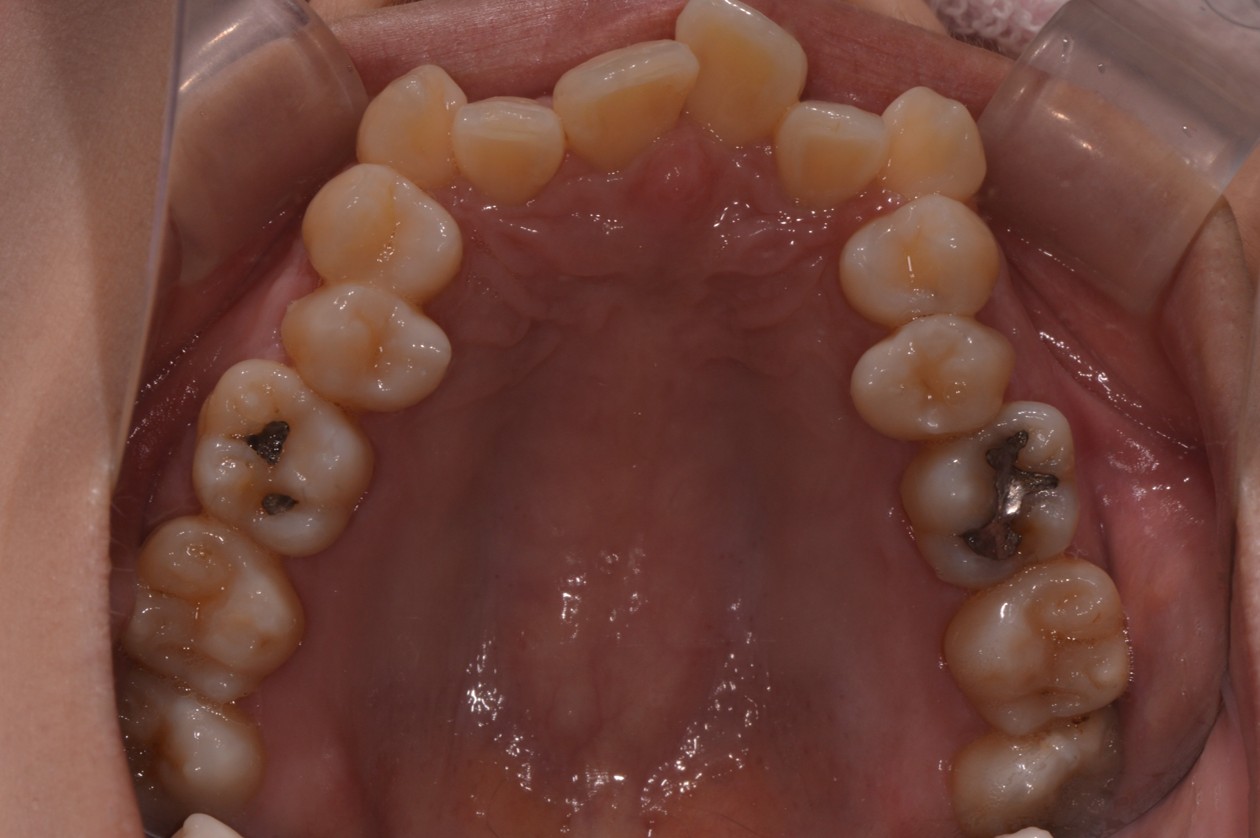

症例1

| 項目 | 詳細 |

|---|---|

| 患者様データ | 30代 女性 |

| 来院時の主訴 | 「上下のガタガタ歯並びと噛み合わせが気になる。」 |

| 矯正法 | 上の歯2本を抜歯しての矯正 |

| 通院期間 | 2年9ヶ月 |

| 治療費 | 総額:1,070,000円(税抜) 【内訳】 精密検査50,000円、メタルワイヤー矯正800,000円、月に1度の調整料5,000円、後戻り防止のリテーナー35,000円×2 |

| リスクと副作用 |

①歯を動かす事による痛みがあります。また、装置に慣れるまでは、口内炎ができやすいです。 ②歯肉が退縮するリスクがあります。装置が全ての歯に付くので、ハミガキが難しくなります。 ③長期的なメインテナンスが必要 |

| ここがこだわりのポイント!☝ |

この患者様の場合、歯並びのガタガタが強かったことや、抜歯したスペースを埋めるのに時間がかりました。ホームケアも大変だったと思いますが、とてもきれいな歯並びに改善することができました。 |